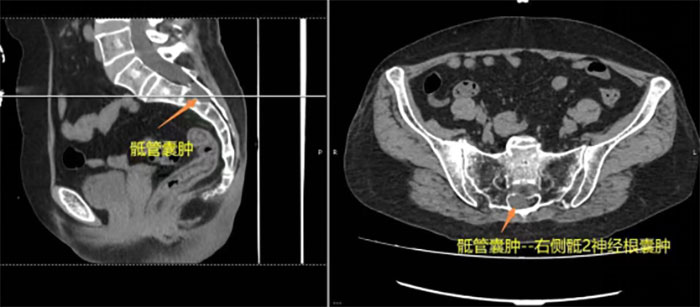

73歲的閆奶奶發(fā)現(xiàn)腰背部腫物十余年,近期出現(xiàn)右下肢疼痛發(fā)涼不適,就診于當(dāng)?shù)蒯t(yī)院行腰椎MRI檢查,提示:骶管囊腫(骶2神經(jīng)根囊腫)、腰背部皮下脂肪瘤,當(dāng)?shù)蒯t(yī)生建議開放手術(shù)治療??紤]到閆奶奶年齡大,基礎(chǔ)疾病較多,開放手術(shù)治療創(chuàng)傷大,術(shù)后腦脊液漏、刀口感染風(fēng)險(xiǎn)大大增加。孝順的子女看在眼里急在心里,先后去過多家醫(yī)院,最終在家人的陪同下,閆奶奶來到滄州市中心醫(yī)院尋求治療。

脊柱外二科(骨二科)主任王麗國接診后仔細(xì)詢問患者病史、詳細(xì)查體后,考慮患者目前右下肢癥狀是由骶管囊腫所致,經(jīng)過脊柱外二科(骨二科)團(tuán)隊(duì)仔細(xì)討論后考慮:患者年齡較大、合并有陣發(fā)性心房顫動(dòng)伴快速心室率等基礎(chǔ)疾病,開放手術(shù)風(fēng)險(xiǎn)較高,術(shù)后并發(fā)癥較多,因此決定首創(chuàng)性使用UBE技術(shù)行骶管囊腫切開術(shù)+腰背部脂肪瘤切除術(shù),用微創(chuàng)的方法解決大問題。